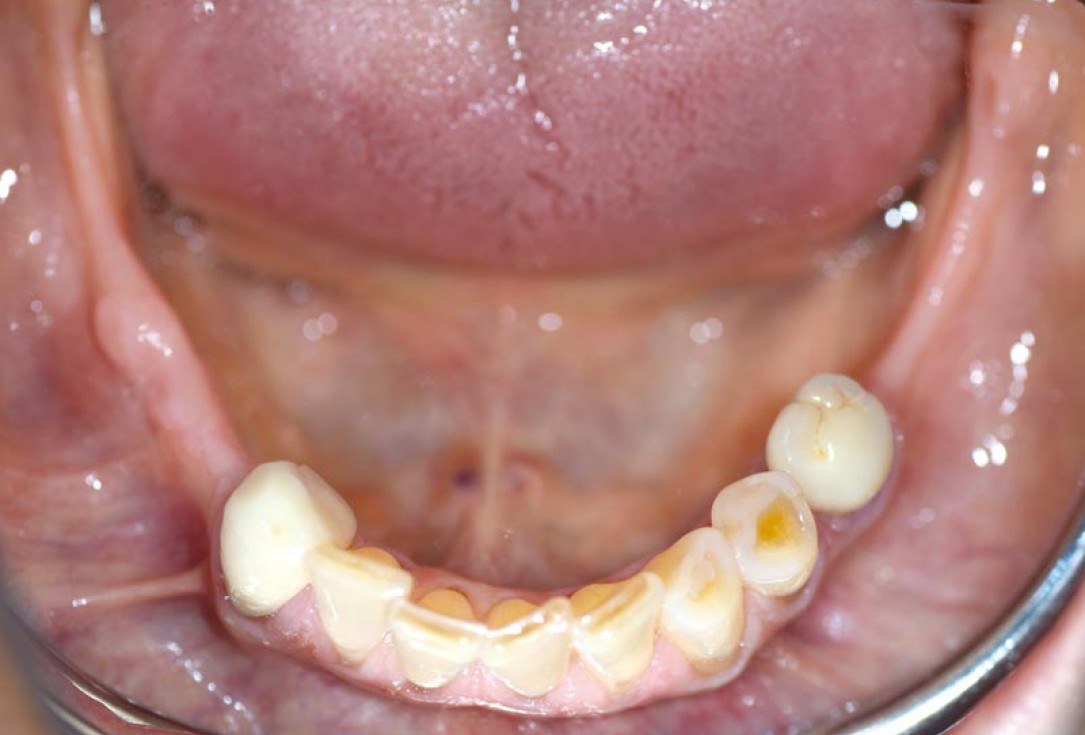

01/14 - Free-end situation in right mandible

Block augmentation with maxgraft® in the mandible - PD Dr. Dr. F. Kloss